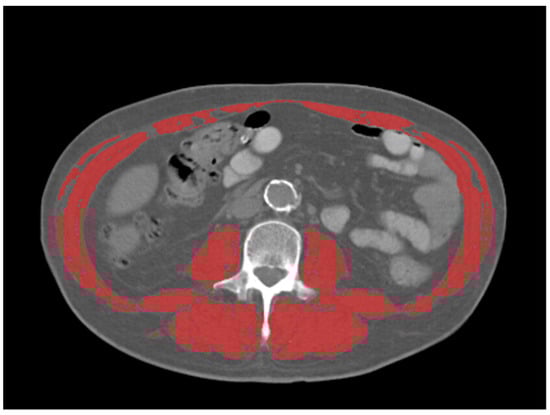

The mean, max, and peak standardized uptake values (SUV) and SUV normalized by lean body mass (SUL), were collected from the primary tumor in each patient, using a common commercially available imaging software (Mirada XD Workstation, Mirada Medical, Ltd., Oxford, UK). SUV were obtained manually with a volume-of-interest (VOI) covering the entire tumor volume as defined by PET. Sarcopenia measurements were taken from the CT component of the 18F-FDG PET/CT. Assessment of skeletal muscle mass was performed at the level of the third lumbar vertebra using Slice-O-Matic (TomoVision, version 5.0, Magog, QC, Canada) Hounsfield units (HU) were used to identify skeletal muscle (threshold −29 to 150 HU) (Figure 1). Skeletal muscle index (SMI) was calculated by normalizing the muscle area (cm2) for the subject’s height in squared meters (m2). SMI cutoff values for sarcopenia were used as follows [15]: SMI of 34.4 cm2/m2 in females and SMI of 45.4 cm2/m2 in males. Image analysis was performed by one radiologist with 5 years of experience in oncologic imaging.

Figure 1. Representative example of skeletal muscle measurements on CT at the level of L3 (outlined in red). Thresholds for skeletal muscle were −29–150 HU.